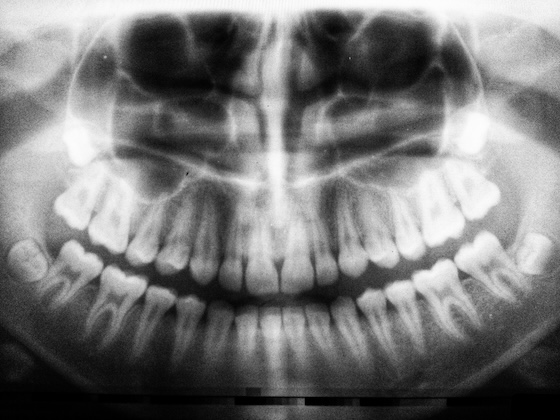

Rentgenologinos tyrimas klinikoje atliekmas radioviziografu. Šis tyrimas atliekamas kai reikia nustatyti dantų, dantų šaknų, juos supančių audinių (periodonto) būklę, įvertinti gydymo kokybę. Kartais būtina atlikti kelias radiogramas. Naudojant radioviziografą vaizdą gauname kompiuterio ekrane, svarbu, kad naudojama technika pacientui duoda apšvitą 90% mažesnę nei anksčiau naudoti neskaitmeniniai radiografai.